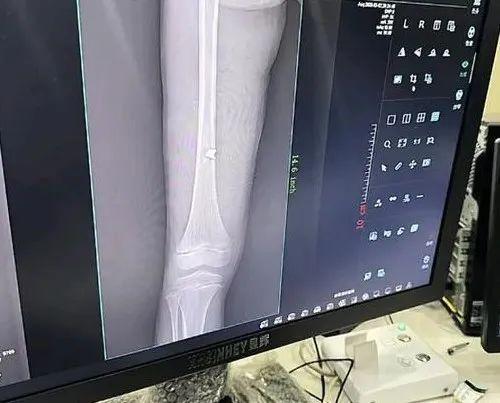

从医院拍的片子,可以看到孩子的左侧股骨内侧,被弹片击中,看着还挺严重的。家属也表示,弹片扎进了骨头里。